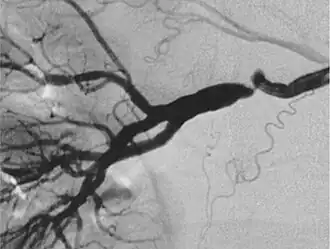

- Fibromusculaire dysplasie van vaten